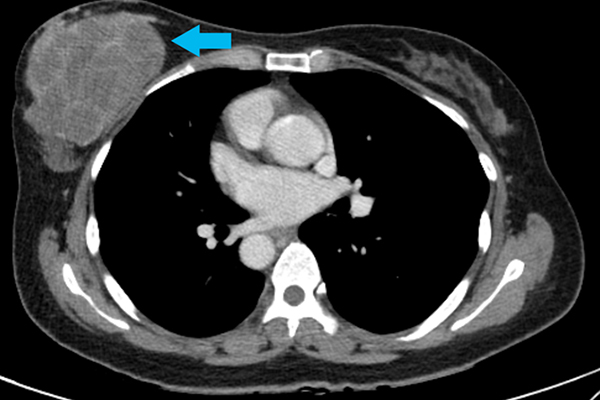

악성 엽상종은 전체 유방암 중 1% 미만인 희귀한 암으로, 드물지만 치명적인 암으로 꼽힌다. 성장이 빠르고 크기가 큰 데다, 재발과 전이 또한 쉽기 때문이다. 아직까지 수술 외에는 효과적인 치료법이 없고, 연구를 위한 적절한 세포주, 동물모델도 부족해 치료제 개발에 난항을 겪는 상태다.